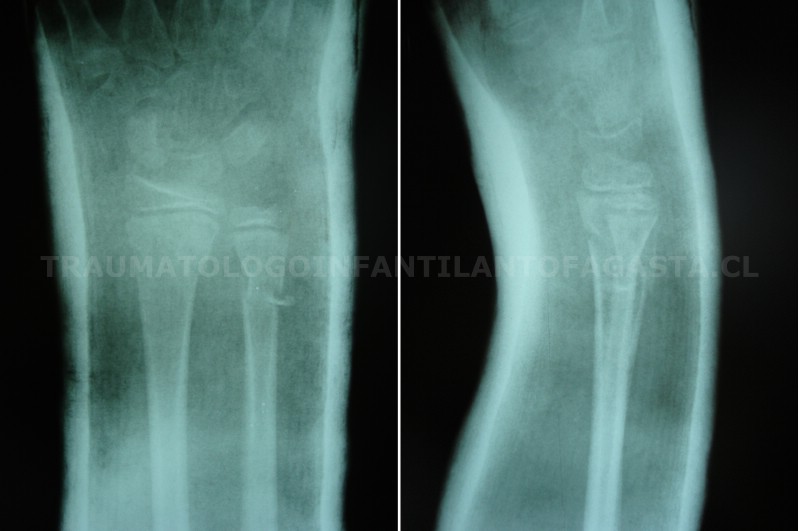

Fractura de codo

Fractura de codo inestable